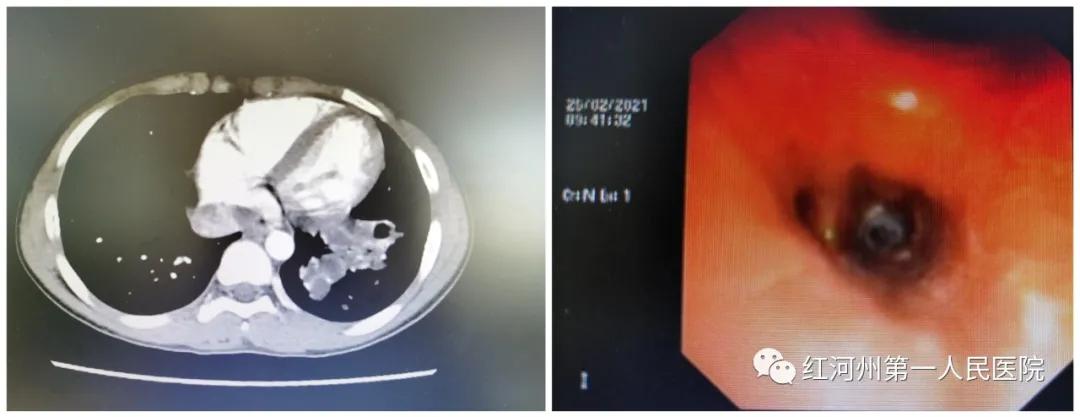

经胸部CT检查提示为

左肺下叶囊状支气管扩张伴管腔内粘液栓

检查影像

进行气管镜检查

手术医师发现其

左下肺基底段开口处

有一环形异物